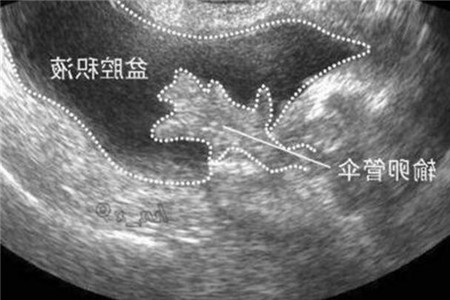

生理性盆腔积液

其实所谓生理性盆腔积液算是比较常见的,简单来说就是在生理期或者是排卵期时出现一些少数的积液。这主要是盆腔在腹腔下面,当腹腔有液体渗出或者是出血时就会导致盆腔积液的出现。